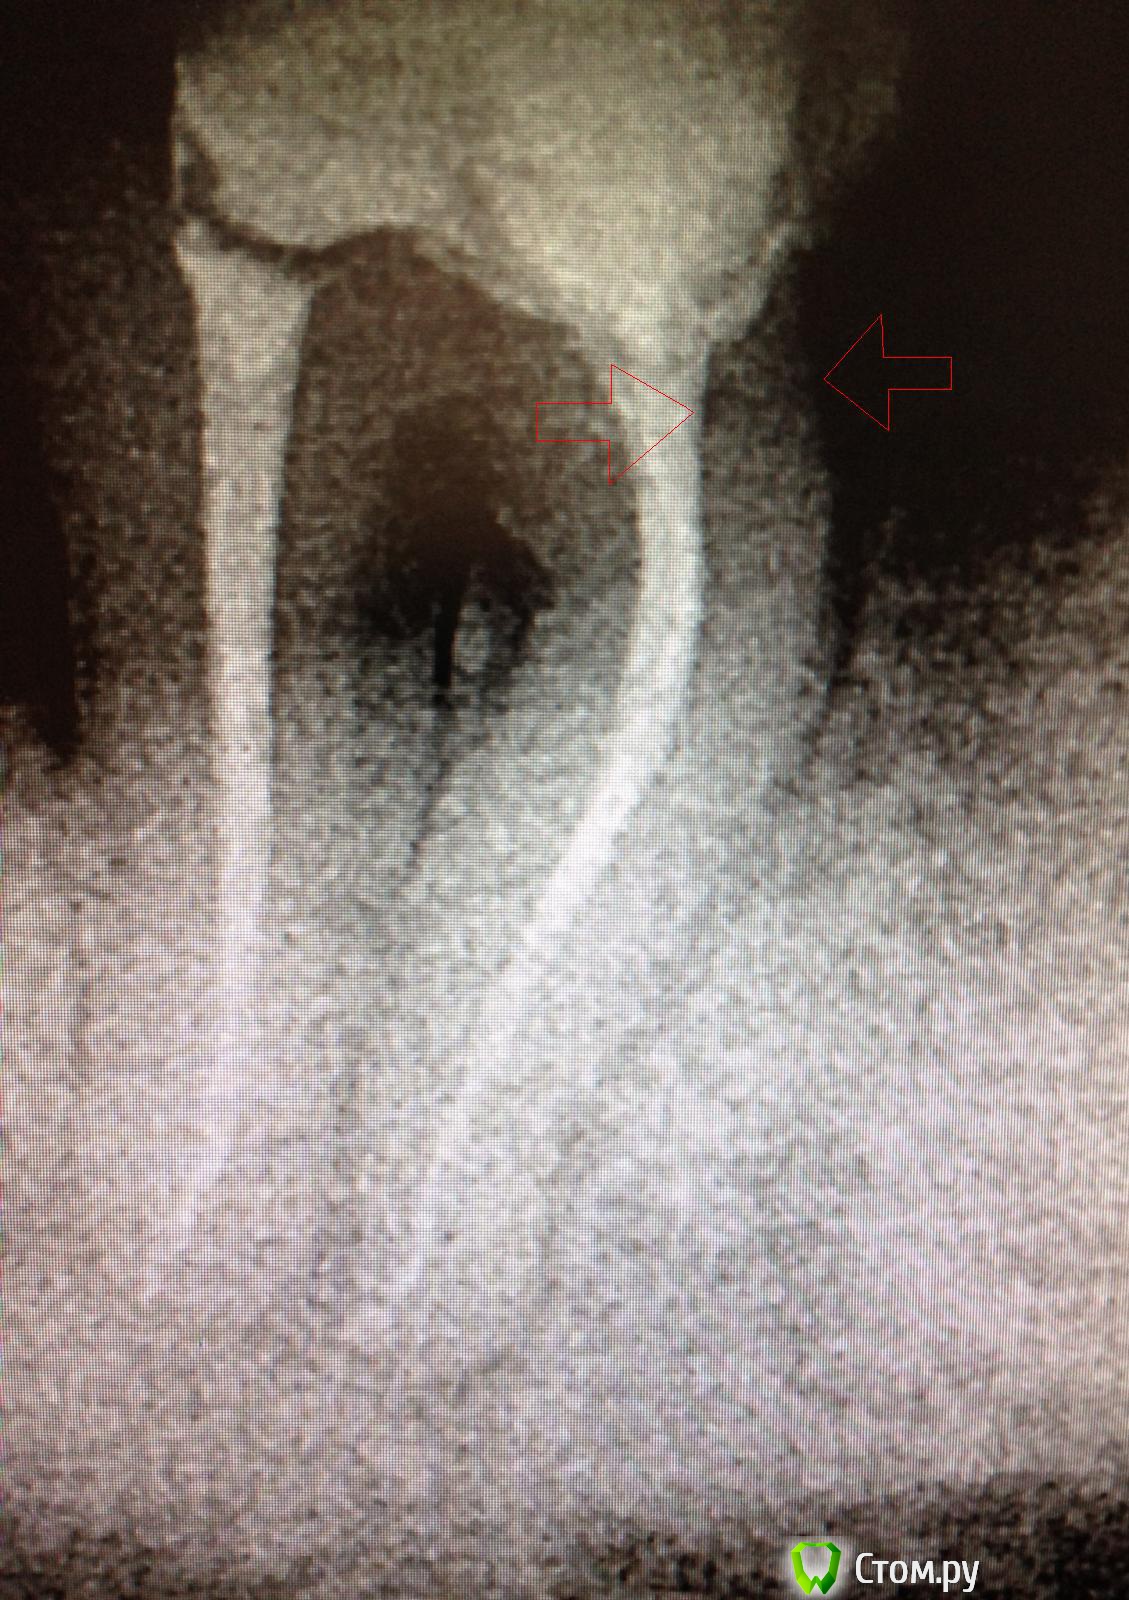

faity Опубликовано 29 мая, 2014 Поделиться Опубликовано 29 мая, 2014 артефакт на снимке или перелом или дельта? Ссылка на комментарий

SSTi Опубликовано 29 мая, 2014 Автор Поделиться Опубликовано 29 мая, 2014 Сильно увеличивал контрастность, чтобы можно было разглядеть что-нибудь. В латераль затекло бы, не думаю , что перелом. Сделаю еще один снимок в следующий раз. Я даже не заметил. Спасибо, что нашли)) Ссылка на комментарий

faity Опубликовано 29 мая, 2014 Поделиться Опубликовано 29 мая, 2014 Сильно увеличивал контрастность, чтобы можно было разглядеть что-нибудь. В латераль затекло бы, не думаю , что перелом. Сделаю еще один снимок в следующий раз. Я даже не заметил. Спасибо, что нашли))пожалуйста и можно на ты) надеюсь всё обойдется Ссылка на комментарий

SSTi Опубликовано 29 мая, 2014 Автор Поделиться Опубликовано 29 мая, 2014 Зубу в любом случае осталось недолго. Косточка тютю))) Ссылка на комментарий